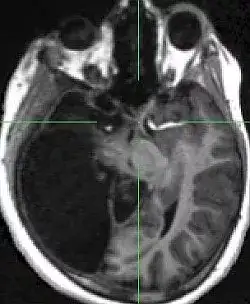

2007 年,《柳叶刀》颁发了一名 44 岁法国男人,因为无诱因左下肢无力,间歇性爆发就诊的病例。大夫查抄他的下肢发现没有异常,思疑是中枢神经系统的问题。于是做了个 CT,成果显示,他有极严重的侧脑室扩张,换句话说,他的脑子只有表层。

这名男纸在出生 6 个月的时辰,因为不明原因的脑积水行脑室分流术,到 14 岁时移除导管及支架。他的大脑在长时候脑积水的侵蚀下,90%已经消逝,IQ 测试只有 75。但他依然正常糊口正常工作,经由过程了本地的公事员测验,在约 30 岁时成婚,已育有一子一女,后代均体健,无神经系统相关疾病等。